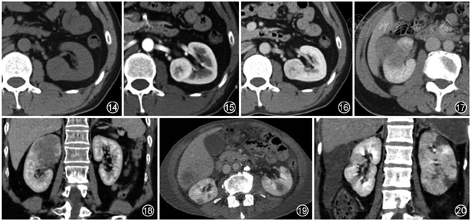

4.淋巴瘤:肾脏是淋巴瘤常见的结外受累脏器,常见非霍奇金淋巴瘤。肾淋巴瘤通常表现为多发性低强化肿块(图18),但也可能表现为腹膜后肿瘤直接侵犯肾脏或肾周软组织肿块、腹膜后多发淋巴结肿大。

5.转移瘤:最常转移到肾脏的原发性恶性肿瘤是肺癌、乳腺癌、胃肠道肿瘤和黑色素瘤。肾转移瘤通常为多灶性和双侧性,呈浸润性生长[4](图19)。在少数情况下,肾转移瘤可能表现为孤立性病变,此时难以与肾细胞癌鉴别。转移瘤多数为轻度强化,强化程度远低于正常肾实质,但部分可为富血供,如黑色素瘤和部分乳腺癌的转移瘤。

6.肾梗死:肾梗死常由肾动脉栓塞引起,房颤、动脉硬化是肾动脉栓塞的高危因素。肾梗死常见的临床表现为急性腰痛和血尿。急性期CT表现为楔形低强化区(图20),晚期局部肾萎缩。当整个肾脏梗死时,肾脏增大,呈低密度。有时病变处近外缘肾皮质可以通过侧支循环而仍有强化,形成“皮质边缘征”。